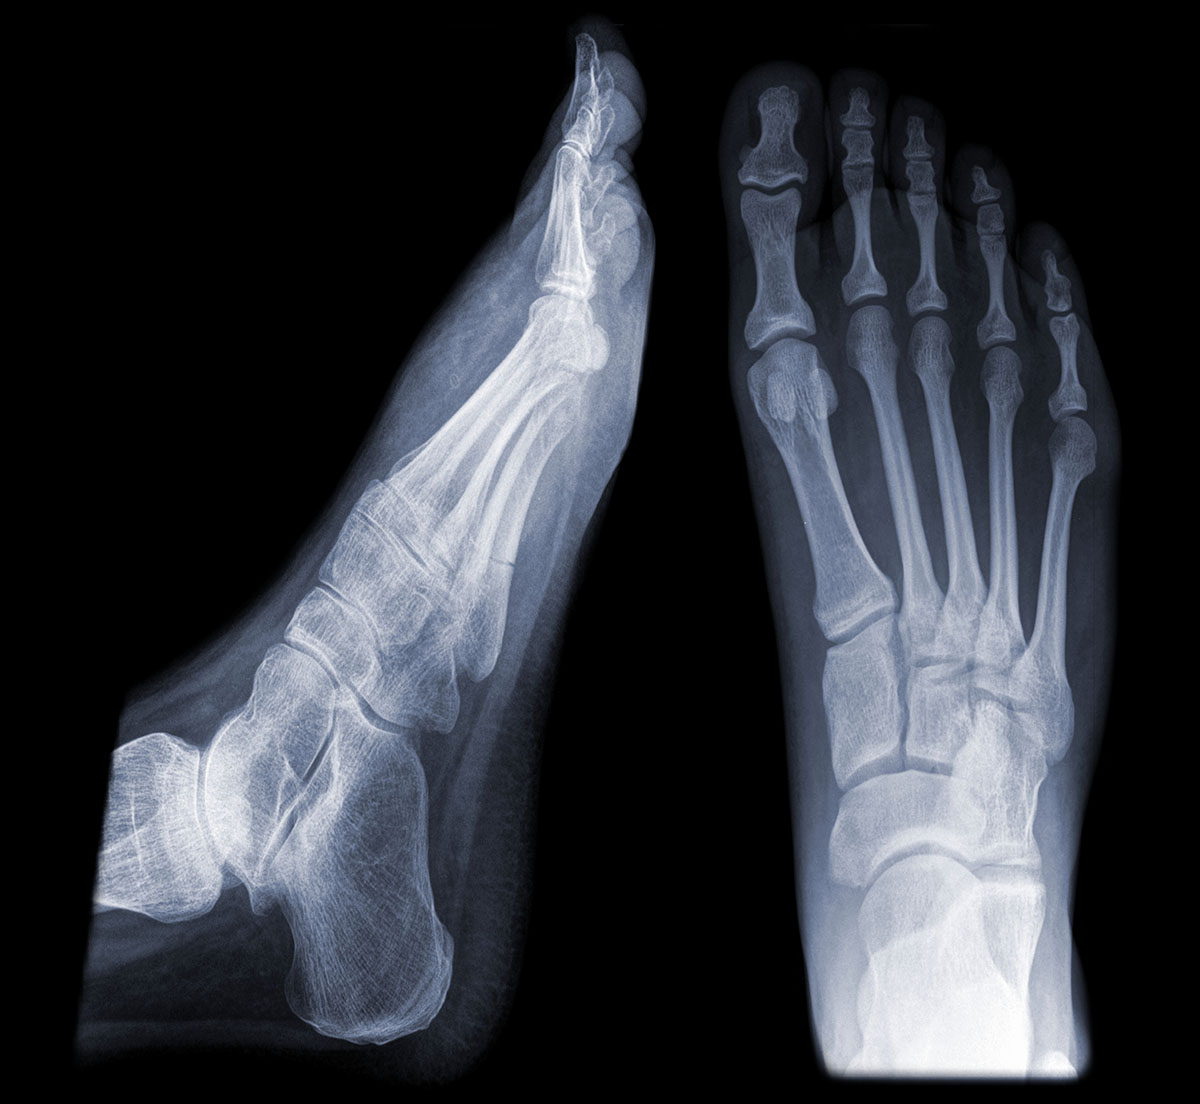

Stress Fracture Symptoms Metatarsal . Pain in the forefoot that develops gradually over time. The bones of the foot. It’s a type of bone fracture (the medical term for broken. Identify clinical signs and imaging findings specific to march fractures, distinguishing them from similar injuries for precise diagnosis. A stress fracture is a small crack in one of your bones. Symptoms of a metatarsal stress fracture include: What is a stress fracture? They're caused by repetitive force, often from overuse — such as repeatedly jumping up and down or. Stress fractures are tiny cracks in a bone. Metatarsal stress fractures can be classified as either high risk. It is usually worse after activity or during. A stress metatarsal fracture occurs when the metatarsal bone fractures due to repetitive stress.

The bones of the foot. Identify clinical signs and imaging findings specific to march fractures, distinguishing them from similar injuries for precise diagnosis. It’s a type of bone fracture (the medical term for broken. Pain in the forefoot that develops gradually over time. Symptoms of a metatarsal stress fracture include: A stress metatarsal fracture occurs when the metatarsal bone fractures due to repetitive stress. A stress fracture is a small crack in one of your bones. It is usually worse after activity or during. Metatarsal stress fractures can be classified as either high risk. Stress fractures are tiny cracks in a bone.

Stress Fracture Symptoms Metatarsal The bones of the foot. What is a stress fracture? They're caused by repetitive force, often from overuse — such as repeatedly jumping up and down or. A stress fracture is a small crack in one of your bones. A stress metatarsal fracture occurs when the metatarsal bone fractures due to repetitive stress. Symptoms of a metatarsal stress fracture include: It is usually worse after activity or during. Stress fractures are tiny cracks in a bone. Identify clinical signs and imaging findings specific to march fractures, distinguishing them from similar injuries for precise diagnosis. The bones of the foot. Pain in the forefoot that develops gradually over time. It’s a type of bone fracture (the medical term for broken. Metatarsal stress fractures can be classified as either high risk.